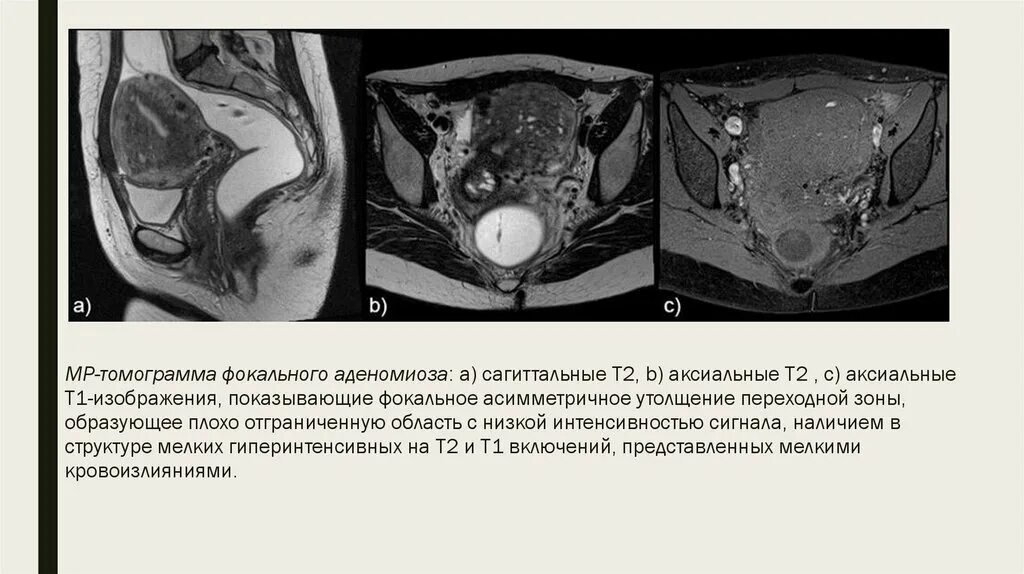

Что такое аденомиоз 1 степени у женщины